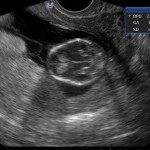

L’ecografia è una tecnica che consente di vedere gli organi del nostro corpo con l’utilizzo di onde sonore ad alta frequenza (ultrasuoni, non udibili dall’orecchio umano) che attraversano i tessuti. La sonda ecografica invia impulsi di onde sonore nel corpo. Quando le onde sonore arrivano al feto mandano degli echi: tali echi (o onde di ritorno) sono trasformati in immagini sul monitor dell’ecografo. Con l’ecografia è quindi possibile osservare in modo dettagliato il feto.

- Perché fare l’ecografia in gravidanza?

Le ragioni più comuni per cui si esegue una ecografia in gravidanza sono: determinare il numero degli embrioni o dei feti, visualizzare l’attività cardiaca fetale, determinare l’epoca di gravidanza, valutare l’anatomia e la crescita fetale, determinare la posizione del feto e della placenta

- Che cosa si vede con l’ecografia?

Nei primi mesi di gravidanza, con la misura della lunghezza del feto, è possibile valutare se lo sviluppo corrisponde all’epoca di gravidanza valutata in base alla data dell’ultima mestruazione, il numero dei feti e la presenza dell’attività cardiaca.

Dal secondo trimestre si misurano altre parti fetali, ed i valori di tali misure vengono confrontati con quelli delle curve di riferimento. Si può così valutare la normalità o meno della crescita fetale. Inoltre periodo si visualizzano la sede di inserzione placentare e la quantità di liquido amniotico.

- E’ possibile rilevare con l’ecografia anomalie fetali maggiori?

La possibilità di rilevare un’anomalia maggiore dipende dalla sua entità, dalla posizione del feto in utero, dalla quantità di liquido amniotico e dallo spessore della parete addominale materna; perciò è possibile che talune anomalie fetali possano non essere rilevate all’esame ecografico. Inoltre alcune malformazioni si manifestano tardivamente (al 7°- 9° mese) e perciò non sono visualizzabili in esami precoci. L’esperienza finora acquisita suggerisce che un esame ecografico routinario, non mirato, consente di identificare dal 30 al 70% delle malformazioni maggiori. Non è compito dell’ecografia la rilevazione delle cosiddette anomalie minori (Linee Guida SIEOG 2006).

- L’ecografia è innocua per il feto?

Gli ultrasuoni sono utilizzati nella pratica ostetrica da oltre 40 anni e non sono stati riportati effetti dannosi, anche a lungo termine, sul feto. Per tale ragione, con le procedure oggi adottate, l’uso diagnostico dell’ecografia è ritenuto esente da rischi. Ovviamente, come in tutte le cose, è bene non eccedere oltre la necessità facendo frequenti esami non necessari.

A fianco alla più tradizionale ecografia eseguita per via transaddominale, risulta particolarmente utile nell’esame ecografico ostetrico e ginecologico la via di accesso transvaginale.

Con questa metodica, utilizzando delle sonde ecografiche appositamente predisposte (per forma e dimensione, e per frequenza di emissione degli ultrasuoni) è possibile controllare la gravidanza nel primo trimestre con una qualità e definizione d’ immagine nettamente superiori a quanto possibile per via transaddominale.

Per eseguire l’ecografia transvaginale non è richiesta la vescica piena, diversamente rispetto a quanto richiesto per l’ecografia transaddominale. L’approccio transvaginale consente di aggirare l’ostacolo dovuto ad un aumentato spessore della parete addominale (obesità). In questi casi infatti la qualità d’ immagine in caso di ecografia transaddominale viene fortemente penalizzata dall’eccessivo spessore del pannicolo adiposo addominale.

Con l’ecografia transvaginale è possibile vedere dopo circa 3 settimane dal concepimento la camera gestazionale nella cavità uterina. Successivamente è possibile visualizzare l’embrione (3-5 mm.) a circa 6 settimane dall’ultima mestruazione (4 settimane dal concepimento) ed a questo periodo è già visibile l’attività cardiaca fetale Anche i primi dettagli sulla morfologia fetale (polo cefalico, abbozzi degli arti) sono visualizzabili più precocemente con l’ecografia transvaginale, risultando essi visibili intorno a 8-9 settimane.

Con l’ecografia dei primi mesi di gravidanza, si può anche valutare la normalità dell’utero (eventuale presenza di fibromi già preesistenti alla gravidanza) e delle ovaie.

Con il finire del primo trimestre per il controllo ecografico di routine della gravidanza la via transvaginale viene poi sostituita dalla via transaddominale.

Successivamente può risultare utile il ricorso all’ ecografia transvaginale nei casi in cui si sospettino delle modificazioni precoci (raccorciamento) del collo dell’utero, come potrebbe verificarsi nei casi di minaccia d’ aborto o di parto pretermine.

In questi casi infatti è possibile con l’ ecografia misurare con precisione la lunghezza del collo uterino. In questi casi inoltre l’ ecografia può anche evidenziare un’ iniziale dilatazione dell’ orifizio uterino interno. Tali modificazioni del collo dell’ utero, valutabili con accuratezza solo con l’ ecografia transvaginale, hanno una grande importanza nel considerare un eventuale rischio di parto pre-termine.